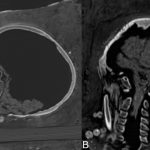

Un equipo de arqueólogos analizó los restos de tres momias egipcias correspondientes al periodo romano tardío —entre finales del siglo III y del siglo...